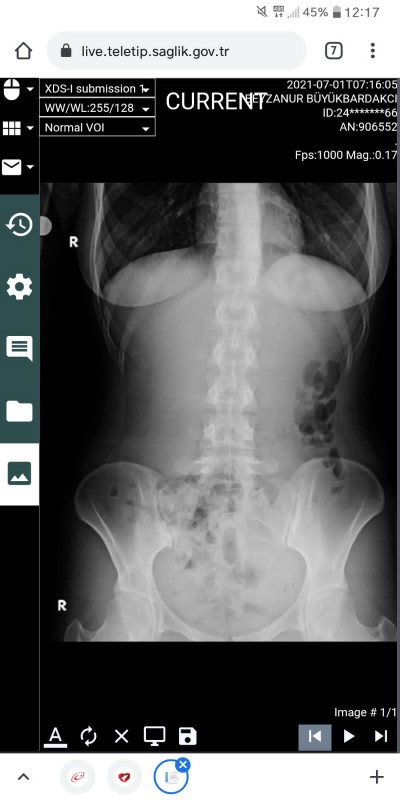

Kizlar rontgende lekeli lekeli biseyler gorunuyor bobregmde tas veya kum varmis doktor dedi rontgende cikarmi

image sizce bunlar ne

Bağırsak gazı :D

Evet canım :) ben röntgen teknisyeniyim kum röntgen de görünmez taş da çok büyük belirgin olması lazım ki çıksın o gördüklerin siyah baloncuklar bağırsak gazı :)

Peki bu kum taş olayı idrar yollarında varsa orada ultrasonla gözükür mü

Zaten ultrasonla yada idrar tahlili ile cikiyor

Aynen canım idrar da görünirse ultrasonla netleştirirler :) çok geçmiş olsun :)